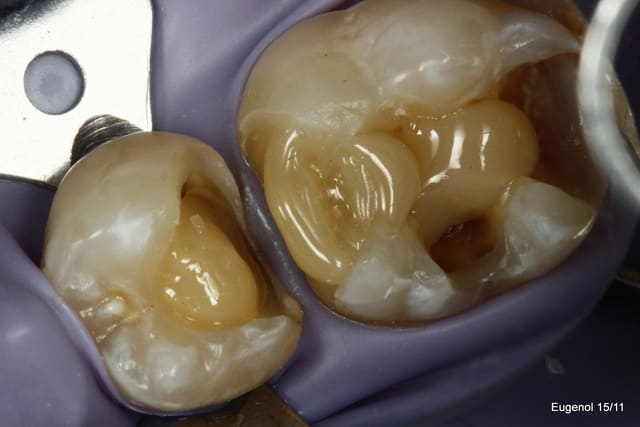

Ben les photos finales c'est après réglage de l'occlusion sinon c'est pas drôle.

Quand on s'appuie sur les cuspides restantes et qu'on donne une morphologie assez naturelle, en général il y a peu de retouche occlusale.

Sinon je fais les sillons secondaire a la sonde.

C'est du compo Enamel HRI en dentine et Esthelite en email qui se sculpte facilement et reste pourtant souple et autolissant...

Le polissage c'est des brossettes chargées en silice, et avec de la pâte à polir.